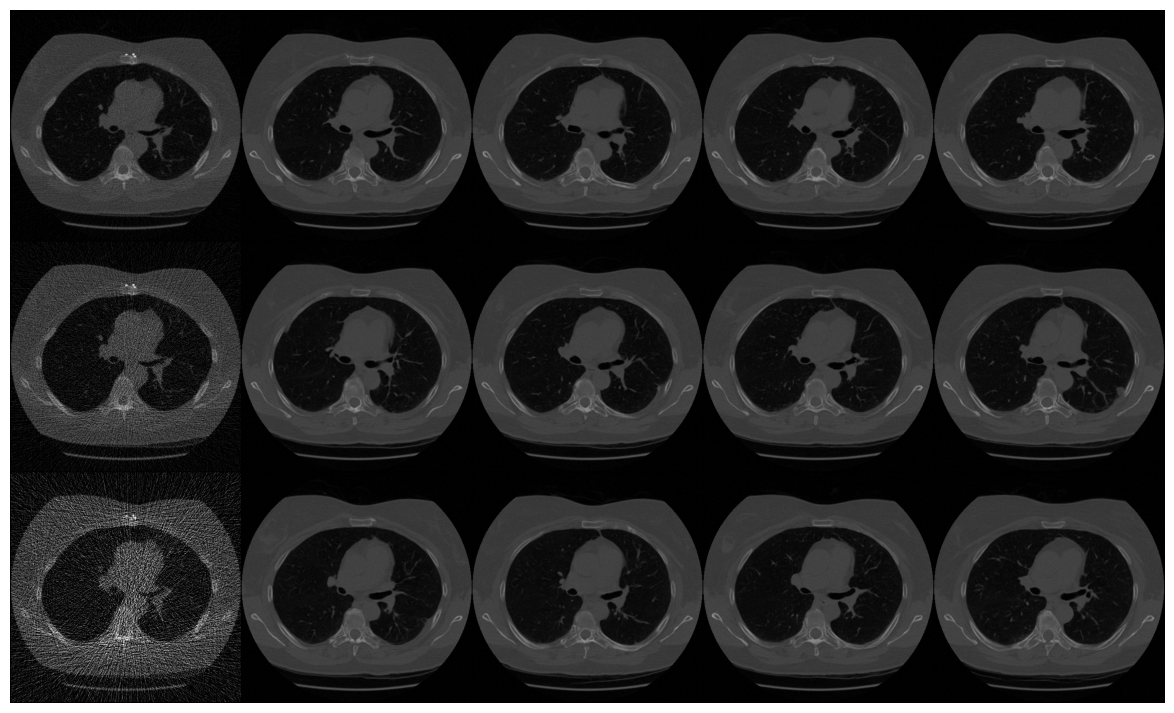

FBP

poisson

gaussian

\(I_0 = 4096\)

\(I_0 = 512\)

\(I_0 = 128\)